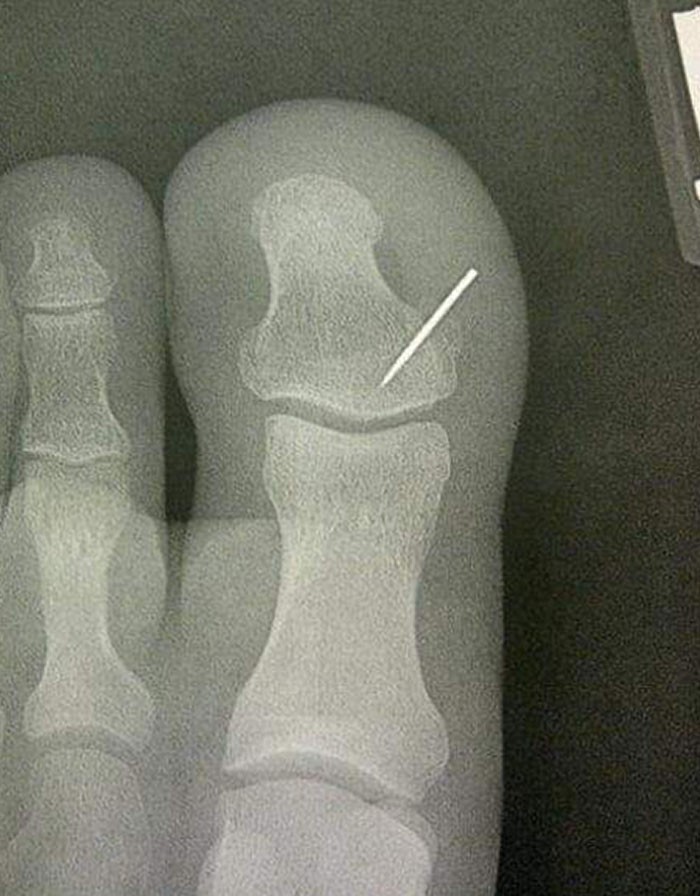

7. "Żona zgubiła igłę. Znalazłem ją kilka dni później."

7. "Żona zgubiła igłę. Znalazłem ją kilka dni później." © FourStringTap